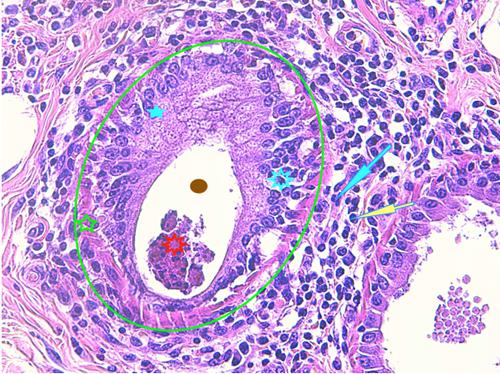

Photo 14 (Hémalun Eosine X 100) peau velue : Dans le derme, les pelotons de

glandes sudorales épitrichiales sont entourés de manchons inflammatoires

associant principalement granulocytes éosinophiles et plasmocytes.

Légendes de la Photo 14 :

- Étoiles rouges : lumière des glandes sudorales apocrines épitrichiales

- Flèches jaunes : infiltrat inflammatoire dermique en manchons péri-sudoraux

Photo 15 (Hémalun Eosine X 40) peau velue : Dans le derme, les pelotons de glandes

sudorales épitrichiales sont entourés de manchons inflammatoires associant principalement

granulocytes éosinophiles et plasmocytes. Leur lumière peut contenir des débris de granulocytes.

Légendes de la Photo 15 :

- Flèche turquoise : granulocyte éosinophile

- Flèche jaune : plasmocyte

- Étoile turquoise pleine : cellule épithéliale glandulaire de la glande sudorale

- Étoile verte : cellule myoépithéliale de la glande sudorale

- Étoile turquoise évidée : cellules inflammatoires dans la paroi de la glande (hidrosadénite)

- Étoile rouge : débris inflammatoires dans la lumière glandulaire (hidrosadénite)

- Rond vert : délimite un peloton sudoral

Photo 16 (Hémalun Eosine X 200) peau velue : Mise en évidence d’un fragment

d’élément figuré vermiforme “fiché” dans la gaine épithéliale externe d’un infundibulum folliculaire.

Légendes de la Photo 16 :

- Double flèche verte : lumière de l’infundibulum folliculaire

- Double flèche rouge : gaine épithéliale folliculaire externe

- Ovale noir : section d’élément vermiforme “fiché” dans la paroi folliculaire